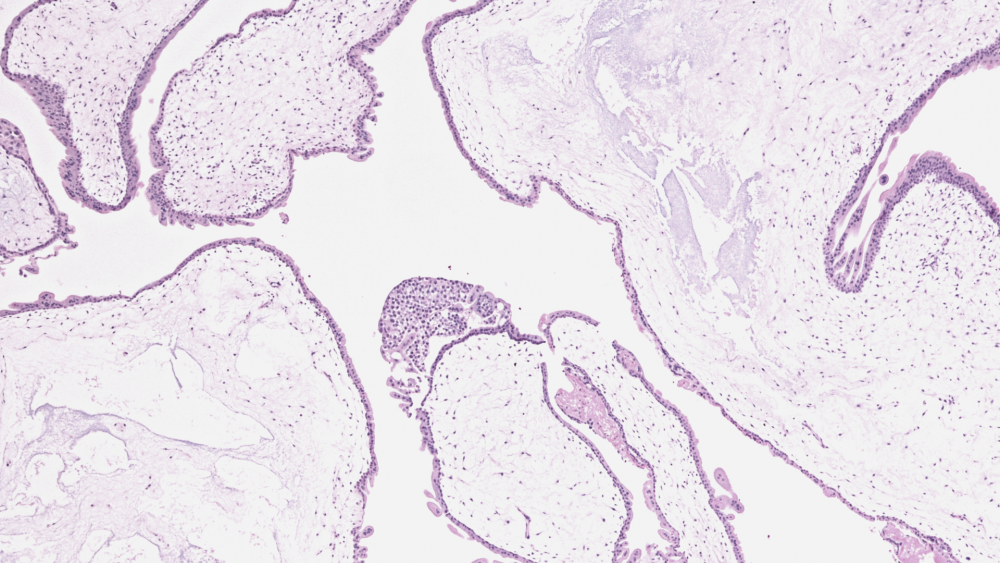

Трофобластические опухоли — это опухоли, появление которых всегда связано с беременностью. Они образуются из трофобластов — клеток, которые образуют внешний слой эмбриона и участвуют в его прикреплении к стенке матке, а также в образовании плаценты.

Трофобластические опухоли